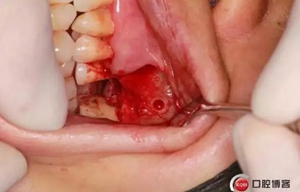

改良式外提升工具盒-外提 科貿(mào)嘉友收錄

六個(gè)月之后